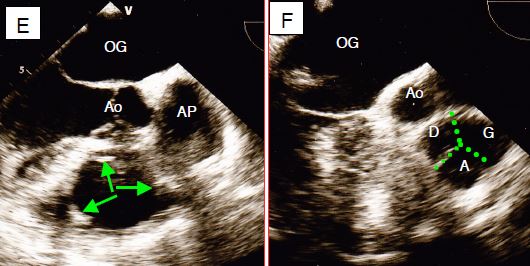

Figure 11.161 : Vues de la valve pulmonaire. Elle est peu échogène parce qu’elle est fine et très antérieure, partiellement masquée par la valve aortique. A : vue mi-oesophage 90° par rotation horaire de la sonde à partir d’une vue 2-cavités du VG ; la flèche indique la hauteur de coaptation des cuspides. B : vue court-axe obtenue à partir d’une vue long-axe de l’aorte ascendante (120-160°) ; les cuspides sont difficiles à discerner. C : Vue court-axe de la crosse aortique à 90° qui offre une vue long-axe de l’AP. D : vue transgastrique du VD 40° ; la valve pulmonaire est en prolongement de la chambre de chasse du VD. E: la vue court-axe de la valve pulmonaire est difficile à obtenir. Dans cette vue, les 3 points commissuraux (flèches vertes) sont à 3 heures, 7 heures et 11 heures. F: vue identique avec illustration des 3 feuillets (D droit, G gauche et A antérieur).

La valve pulmonaire est fine, peu échogène et la plus antérieure des valves, ce qui rend sa visualisation difficile en ETO. Son plan est pratiquement perpendiculaire à celui de la valve aortique: lorsque l'on voit une des deux valves en long-axe, l'autre est en court-axe. Quelques vues permettent une bonne appréciation de la valve pulmonaire (Figure 11.161).